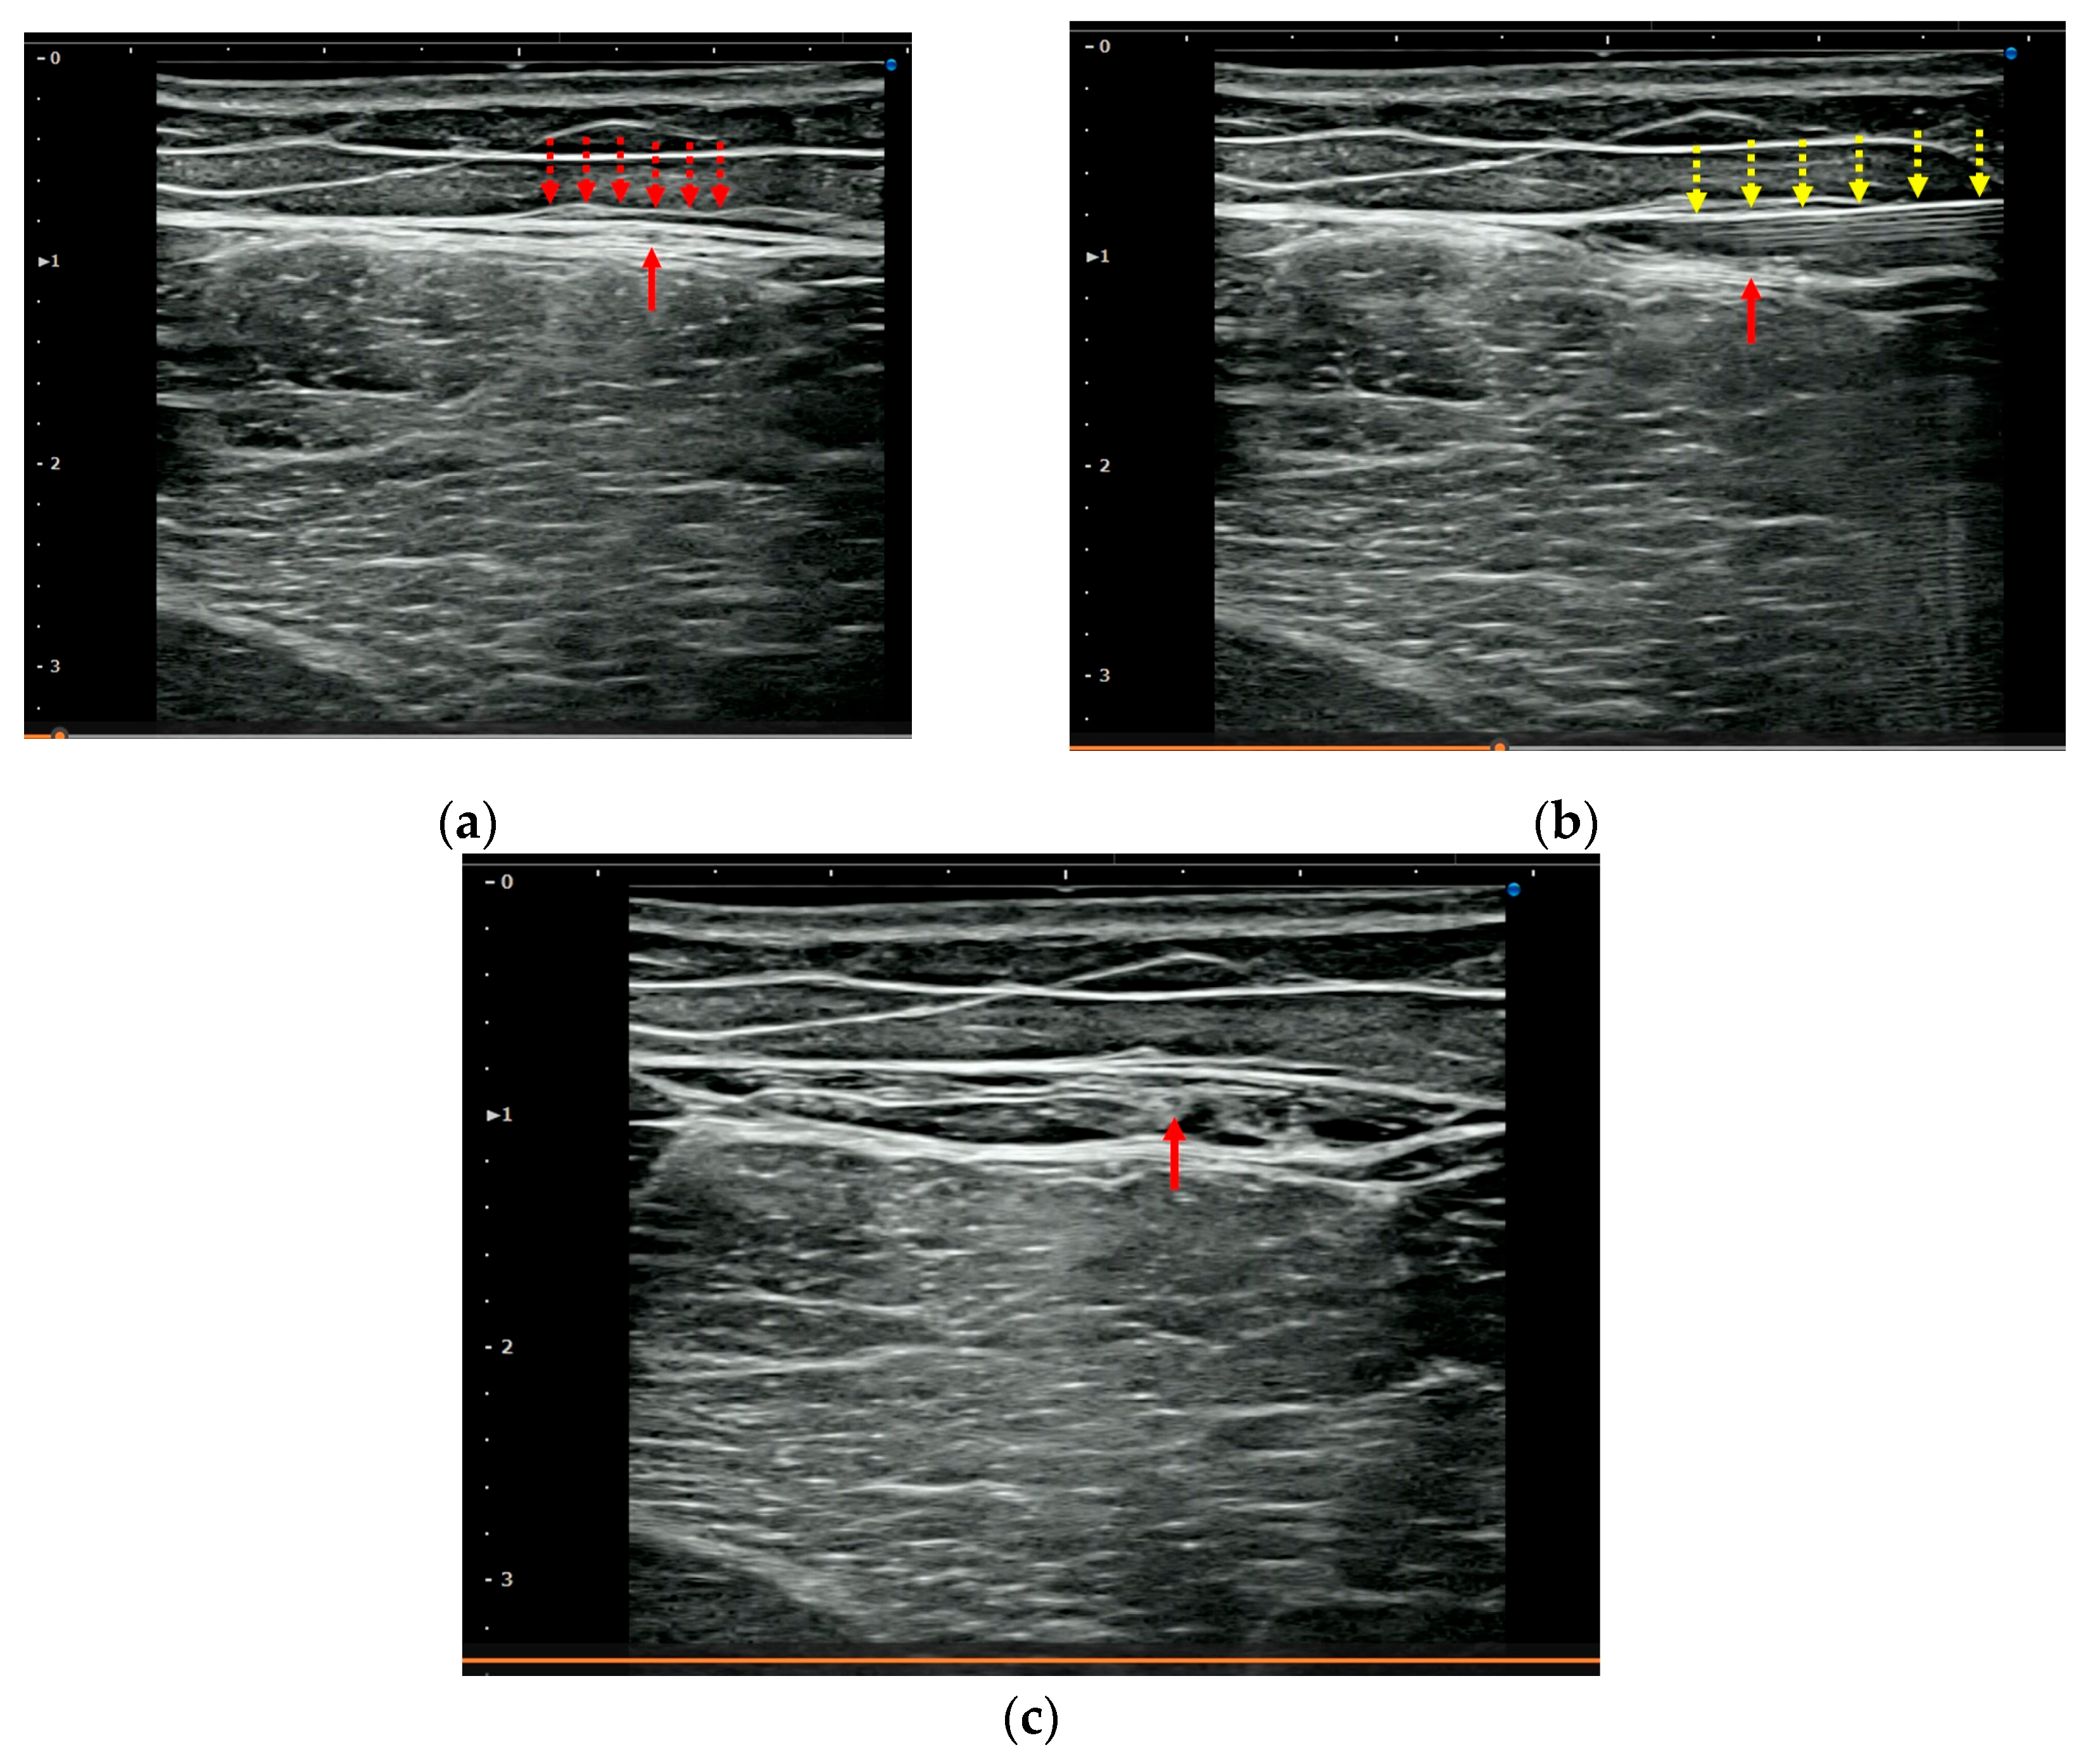

2.5. US-Guided Hydrorelease

3.3. US Imaging and Sonopalpation